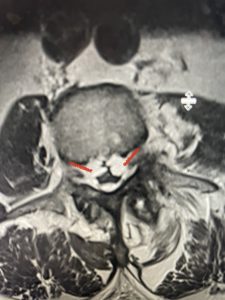

Epidural lipomatosis is a relatively rare condition where normally present fat in the epidural space is hypertrophied and can cause severe thecal sac compression. It is generally deposited more in the lateral and dorsal epidural space. This can be caused by long term steroid use and obesity, but also can be idiopathic. He had done well until more recently had developed low back pain with bilateral thigh pain and numbness. He had difficulty walking because of the pain. A new MRI (Fig 5) revealed that he had developed severe degeneration of the L1-2 segment above his prior decompression and fusion with a large extruded disc/osteophyte, right greater than left with severe thecal sac compression. He also had some residual T12-L3 residual epidural lipomatosis.

He had failed conservative treatment consisting of neurontin, physical therapy and epidural injections. He underwent revision laminectomy T12-L3 to decompress and explore prior fusion. He did have significant epidural fat encountered particularly at L1-2. The fat in epidural lipomatosis has a much more firm, globular texture. It takes a while to search within the fat, gently dissecting with a Penfield 4, to finally find the thecal sac! We encountered a large subligamentous extruded fragment lateral to the thecal sac on the right above the take off of the L2 nerve root. We removed any more residual fat at the L2-3 level and T12-L1 and decompressed the sac well. On exploration of the prior fusion it was fairly solid, but had some gaps at L2-3 fusion mass. Therefore we added a T12-L3 in situ fusion to augment those gaps and because we were at the thoracolumbar junction we extended fusion to T12. Post operatively he had relief of his leg pain.

(Figs 5a): Sagittal (a) and axial (b) T2-weighted lumbar MRI demonstrating status post lumbar decompression and insitu fusion L2-5 now well decompressed (blue dash) with development of new (red arrow) severe stenosis and with superimposed right L1-2 disc herniation (blue arrow)

(Figs 5b)